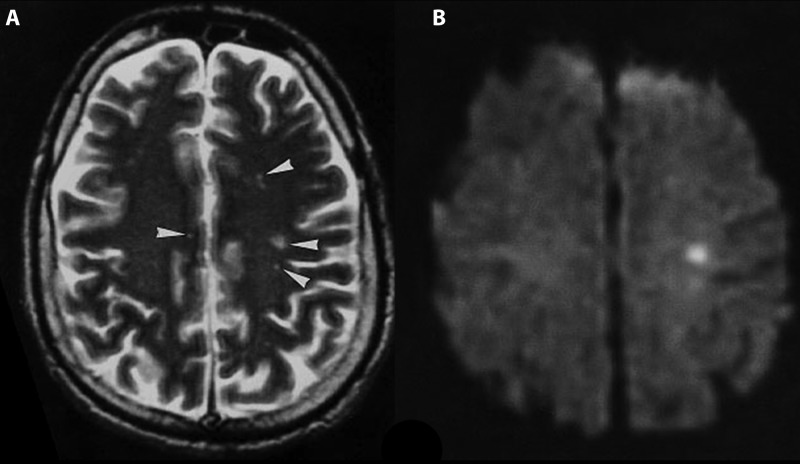

尼帕病毒感染后脑炎的核磁共振图像(图源:参考资料 1)